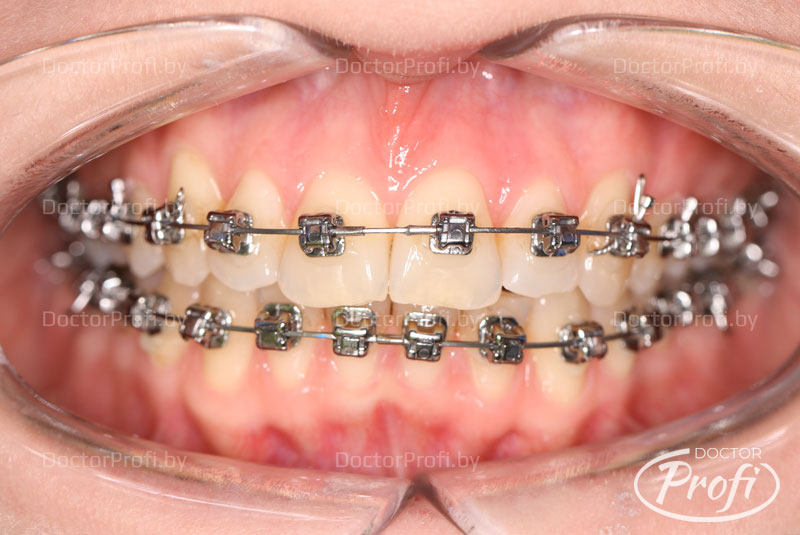

Исправление глубокого дистального прикуса брекет-системой Damon

• Проведена коррекция прикуса без удаления Зубов. Улучшена форма зубных рядов и положение зубов.

• Ортодонтическое лечение проводилось брекет-системой Damon Q.

Срок лечения составил 12 месяцев. В результате проведенного лечения пациентка обрела красивую улыбку, правильный прикус, ровные и здоровые зубы.

После